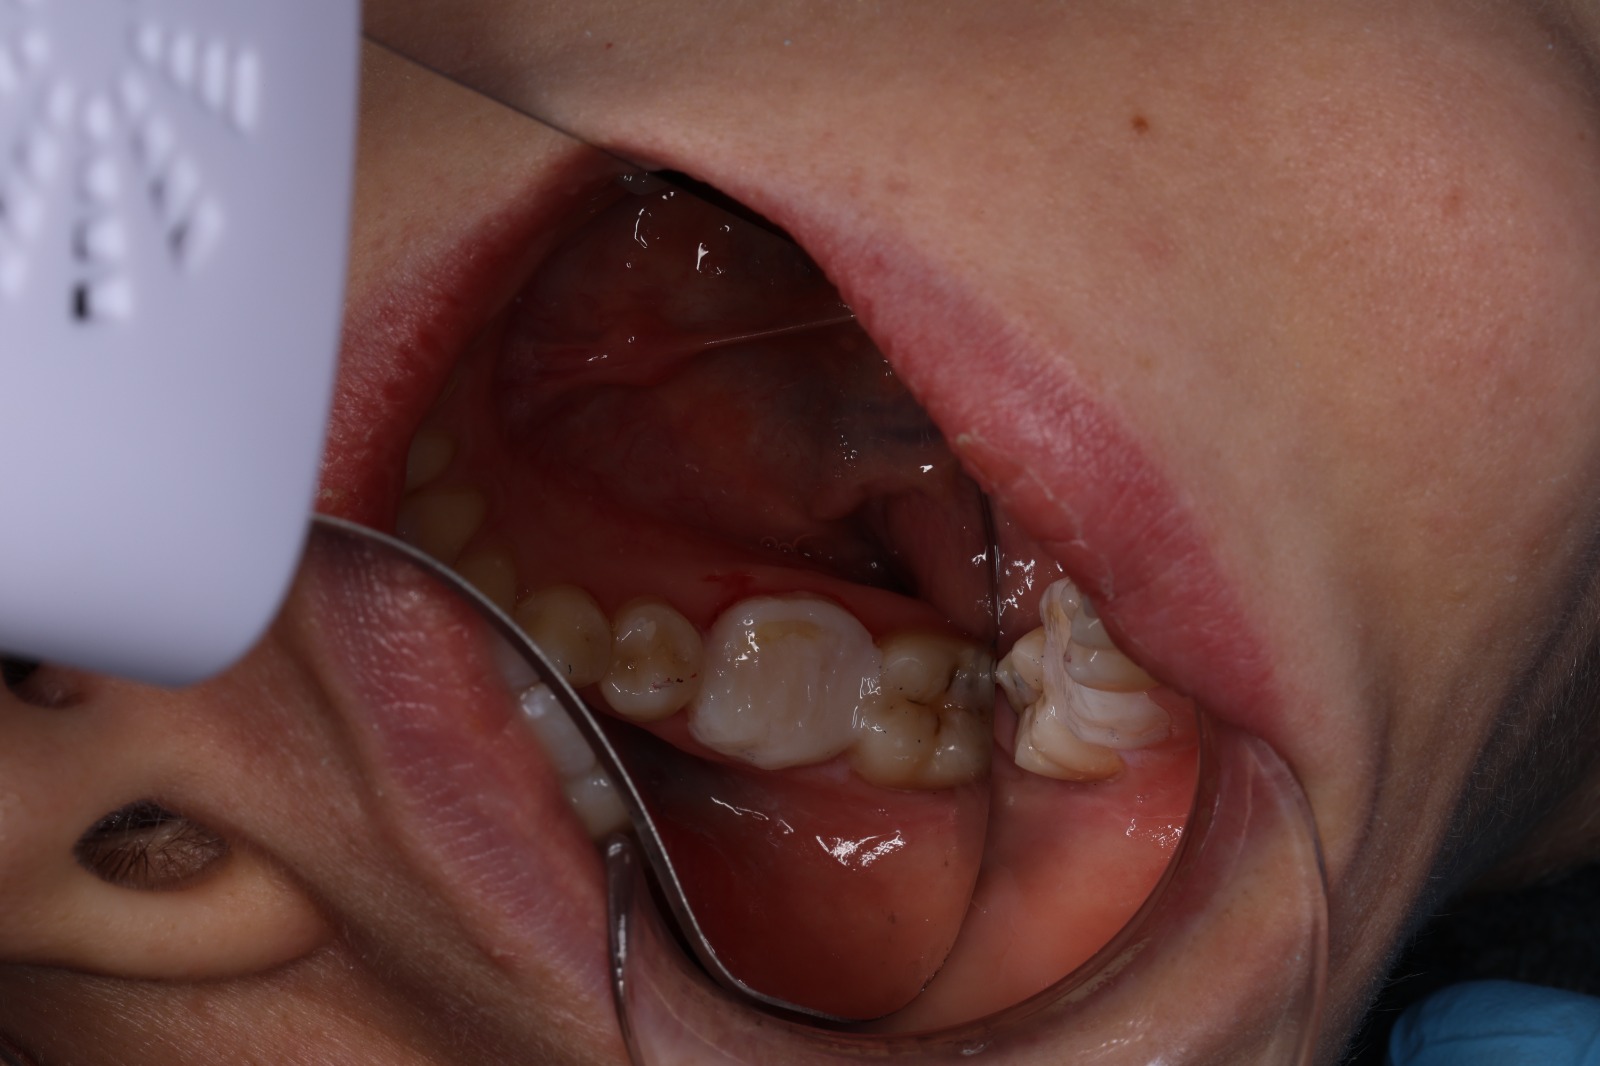

A dull ache that wakes you at night, a sudden jolt when sipping hot coffee, pain on biting, or a small pimple on the gum — all of these may point to inflammation or infection inside a tooth. Modern root canal therapy aims for something simple and vital: remove the infection, preserve the tooth, and bring you relief.

Inside every tooth lies a narrow chamber that contains nerves and blood vessels — the dental pulp. When deep decay, a leaking filling, or trauma allows bacteria to reach this inner space, the pulp becomes inflamed and then infected. The result is pressure, sensitivity, and often an unmistakable throbbing pain.

Some people wonder whether a filling would be enough. Unfortunately, once infection reaches the nerve space, a filling alone cannot stop it. A root canal is the reliable, tooth-saving way to remove the cause and preserve your natural tooth.